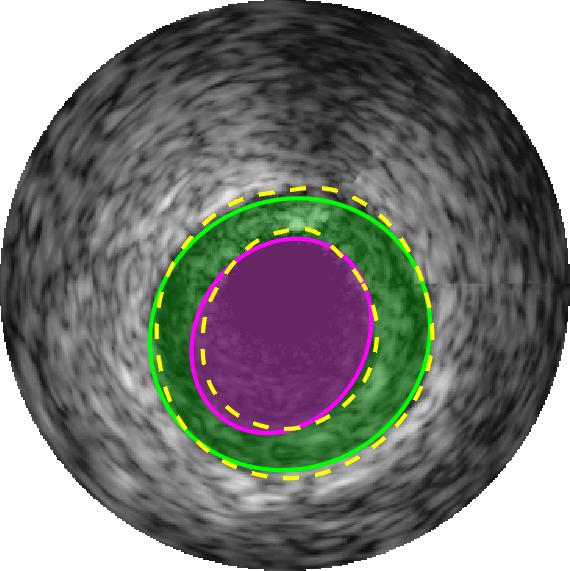

Qualitative evaluations are illustrated in Figure 4 and show the successful segmentation results of the proposed EREL selection strategy for 20 IVUS frames. The lumen areas are highlighted by the magenta colour while the media regions are green. Also, the manually annotated contours for both lumen and media are drawn as yellow dashed lines. As we can see, the chosen frames contain a variety of lumen and media morphologies.